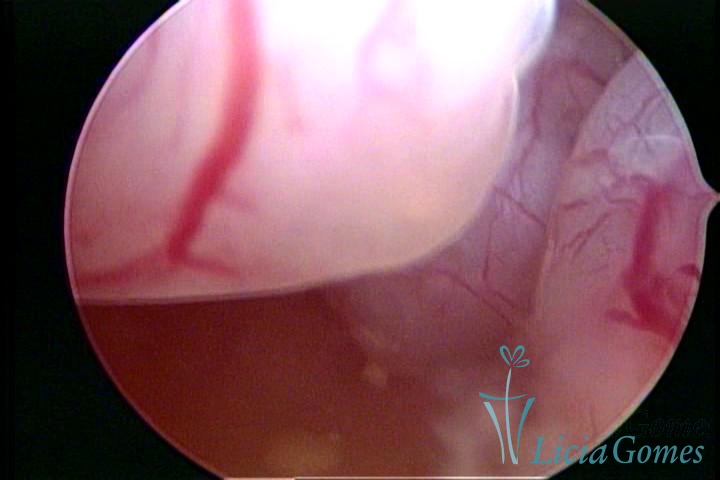

A histeroscopia permite analisar as características da superfície endometrial, não podendo avaliar a profundidade ou o grau de invasão miometrial.

Este pode apresentar uma gama variável de aspectos macroscópicos, com aspecto pseudopolipoide; lembrando tecido cerebroide ou com reação deciduoide;a vascularização superficial é mais evidente e com vasos em formatos de saca-rolha ou espirais visualizando também a vascularização com atípias, com aumento do calibre dos vasos superficiais, pode ser encontrado também tecido em necrose, poderá haver um pequenos dendritos (papilomatoso).